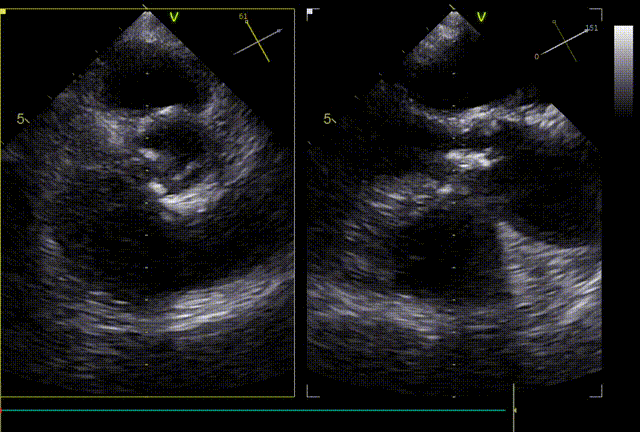

术前超声:

球扩后超声

发生瓣叶切割,无窦侧瓣叶切割,Type0结构形变为类三叶瓣结构。

超声显示人工瓣膜工作良好,微量瓣周漏,术后一周顺利出院,术后随访无并发症,恢复良好。